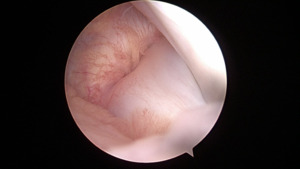

The lateral meniscal tissue appeared hypertrophied and was noted to be a Wrisberg-type discoid variant (Figure 8).